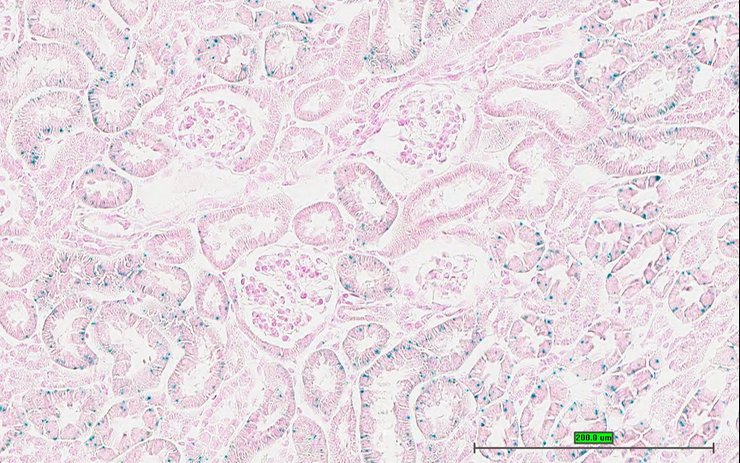

Specimen UC Davis_1880876: postnatal adult; Haaotm2b(KOMP)Mbp/Haao+ (more )

TS28: metanephros Present UC Davis_1880876 kidney

TS28: metanephros Present UC Davis_1880877 kidney

TS28: metanephros Present UC Davis_1880871 kidney

TS28: metanephros Present UC Davis_1880872 kidney